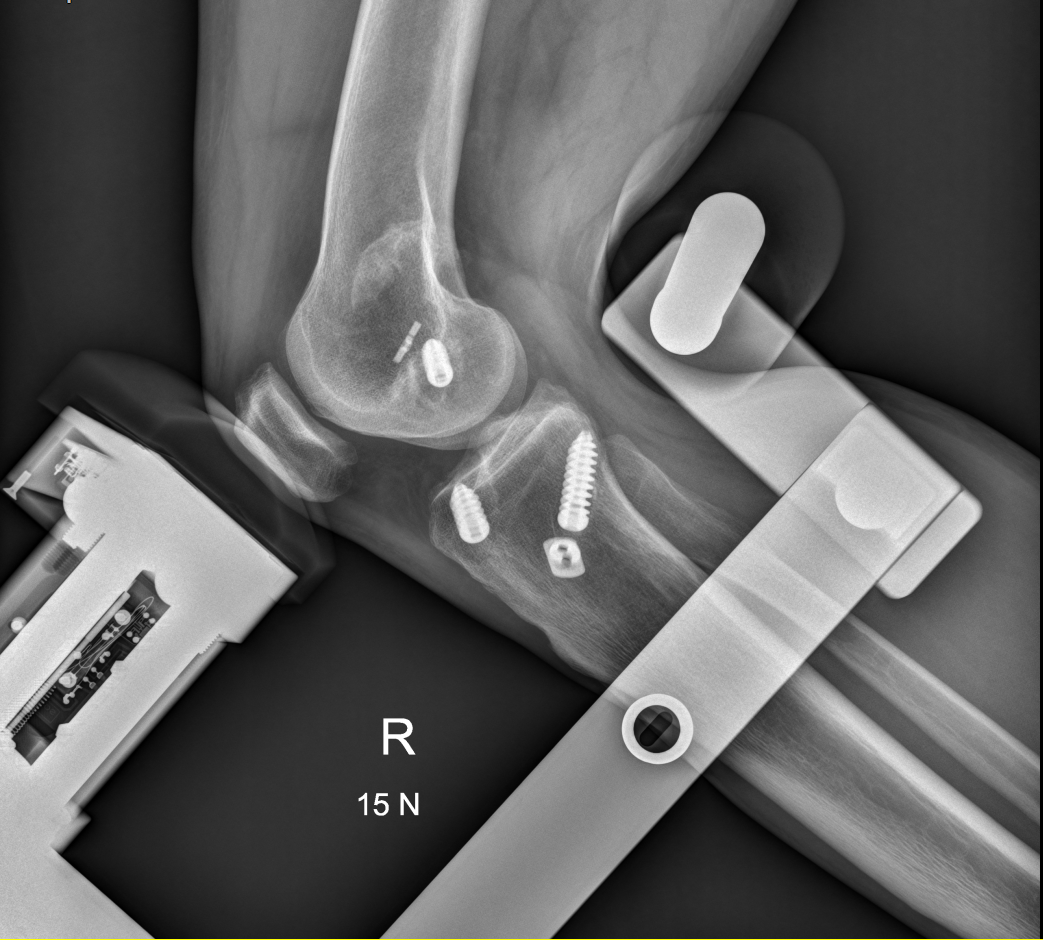

Przykład projekcji wykonywanej w RTG stresowym: Staw kolanowy w projekcji bocznej.